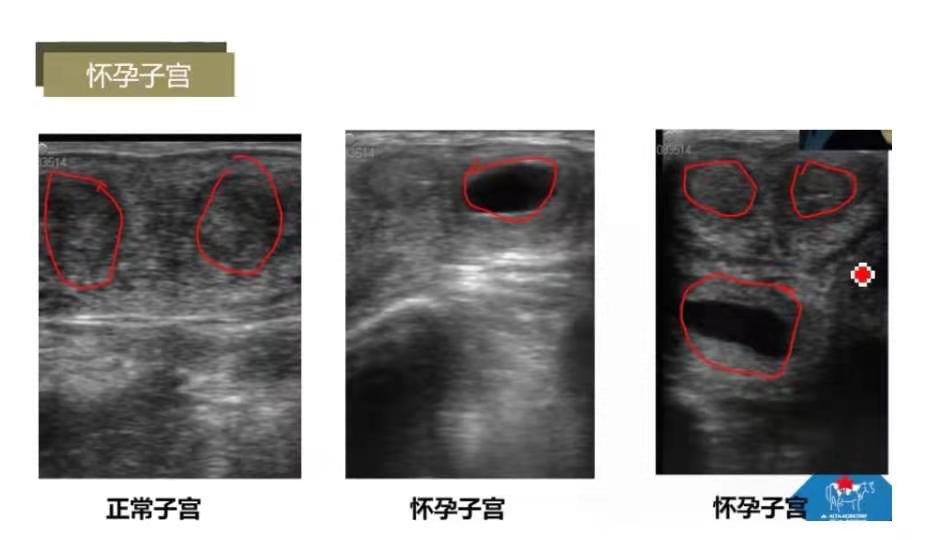

怀孕子宫:正常子宫呈灰色;怀孕子宫一侧角呈黑色,预示可能怀孕;2个角呈灰色,下面呈黑色。

怀孕子宫:怀孕30天子宫空腔内黑色为胚胎,直径1cm左右;33天胚胎直径为1.3cm左右,可检测到胎心;39天胚胎直径2cm左右。